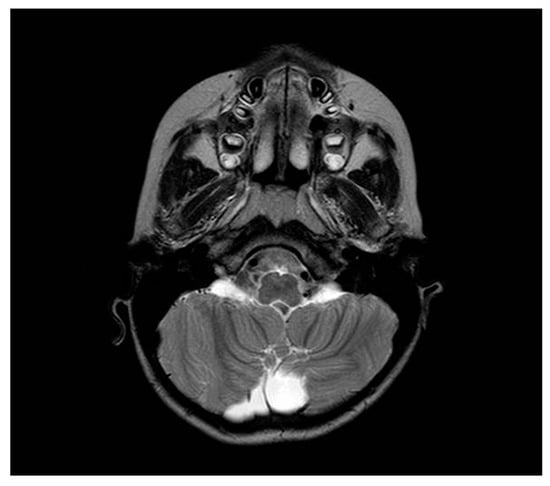

| Our patient | 46, XX, der(8)del(8)(p23.1)invdup(p12p23.1) | + | Developmental and speech delay. No meaningful sentences. Hypotonia. Hypothyroidism. Prominent forehead, arched eyebrow, thin nose with rounded tip and anteverse nostrils, flat filter, thin down-turned lips, slight micrognathia, low-set posteriorly rotated ears. Single palmar crease on the right hand and bilateral IV-V fingers clinodactyly. Hypertrichosis, previous sacrococcygeal fistula sign. Extra-rotation of the lower limbs, varus position of both the knees, flat feet. Bilateral cutaneous dimples on both elbows and knees, shield chest, inverted nipples, winged shoulder blades. Emotiveness, impulsiveness, decreased attention span. Dilatation of lateral ventricles, pineal gland’s small ectasia, moderate cystic cisterna magna’s ectasia, retrocerebellar cystic ectasia. Global chorio-retinic dystrophia, pale papilla with clear boundaries, peri-papillar pigmentary ring. Sialorrhea and extravelic palatin tonsils, ogival palate, type C tympanogram with absent stapedial reflex on the left. |